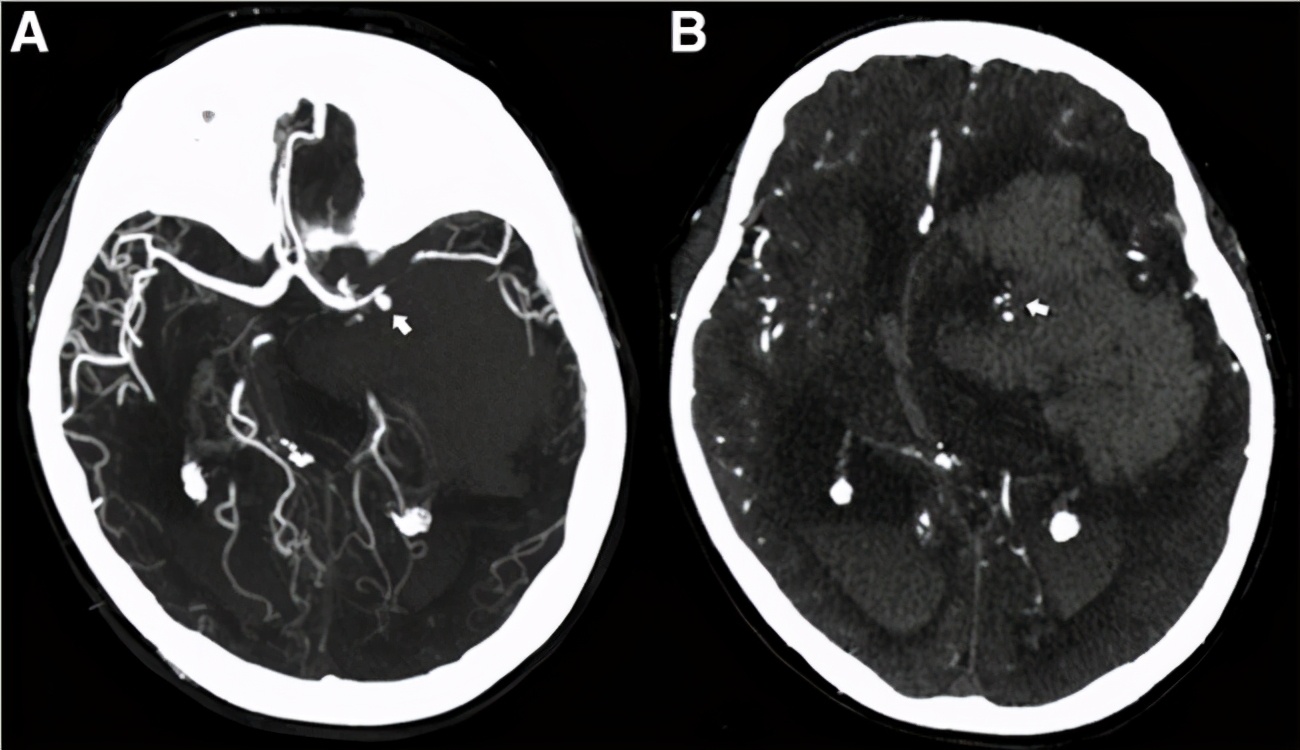

血管造影(DSA)作为补充检查对于腹膜后肿瘤有时起到至关重要的作用。不仅可以显示肿瘤的血流供应情况,对于肿瘤周围的血管毗邻有清晰的认识在研究中,我们发现主要侵犯的血管包括下腔静脉(IVC),腹主动脉,髂血管,肠系膜上动脉。

对于一些直径较大的,血供丰富且单一的肿瘤,术前对肿瘤栓塞可以缩小肿瘤体积,减少术中出血,降低手术难度。同时应当警惕栓塞血管后导致肿瘤坏死,刺激肿瘤细胞再次增殖,加快肿瘤的生长。